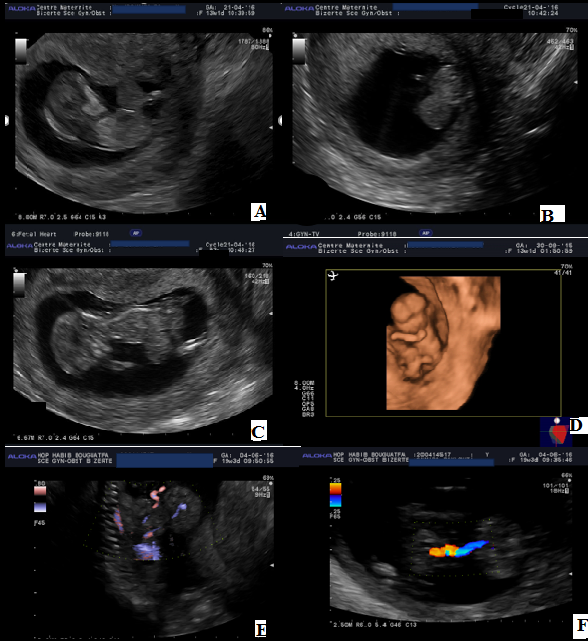

Nous illustrons à travers ce cas l'utilité du dépistage précoce des malformations fœtales au sein d'une unité de diagnostic anténatal, à travers les images d'une omphalocèle diagnostiquée au premier trimestre de la grossesse. Il s'agit d'une patiente âgée de 42 ans, G2P1, ayant fait une première échographie à 12SA+4 jrs montrant une omphalocèle (A,B,C,D). Les informations sur les différentes investigations ont été expliquées à la patiente, qui a décidé de poursuivre la grossesse. Une amniocentèse a été réalisée à 16 SA en vue d'un caryotype. La patiente reconsulte à 19 SA pour réévaluation échographique et interprétation des résultats du caryotype. L'échographie a montré une omphalocèle mesurant 4cm de diamètre, avec un collet à 14,3 mm, contenant le foie et l'estomac (E,F). Le résultat du caryotype révélait une trisomie 18. Une interruption médicalisée de la grossesse a été demandée par la patiente.